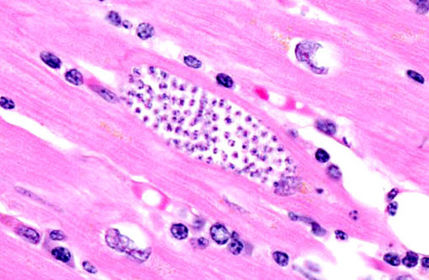

TRICHINELLA SPIRALIS - keeritsuss Kapseldunud vastsed vöötlihaskoes Histoloogiline preparaat